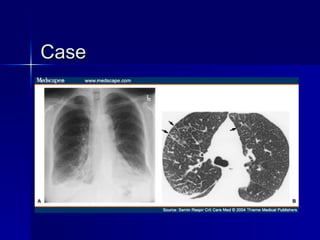

Case 50yo woman  presents with 1 week of fever, chills, chest pain, cough, dyspnea and paresthesias in LE   PMHx: bronchial asthma (7 yrs), allergic rhinitis   PE: 100 F, HR 98, BP 120/70, RR 16/min wheezes/ rhonchi bilaterally mild peripheral weakness in LE sensory dysesthesia in stocking distribution bilaterally

Case Lab: WBC 12.8 (N 30%, L 25%, Eos 40%) Blood/sputum cultures: negative ANA neg, p-ANCA + 1:20 CXR: patchy bilateral infiltrates

Churg-Strauss: Criteria- 4/6 Asthma Eosinophilia (>10%) Mono/ Polyneuropathy Pulmonary Infiltrates – Non-fixed Paranasal sinus abnormality Extravascular eosinophils